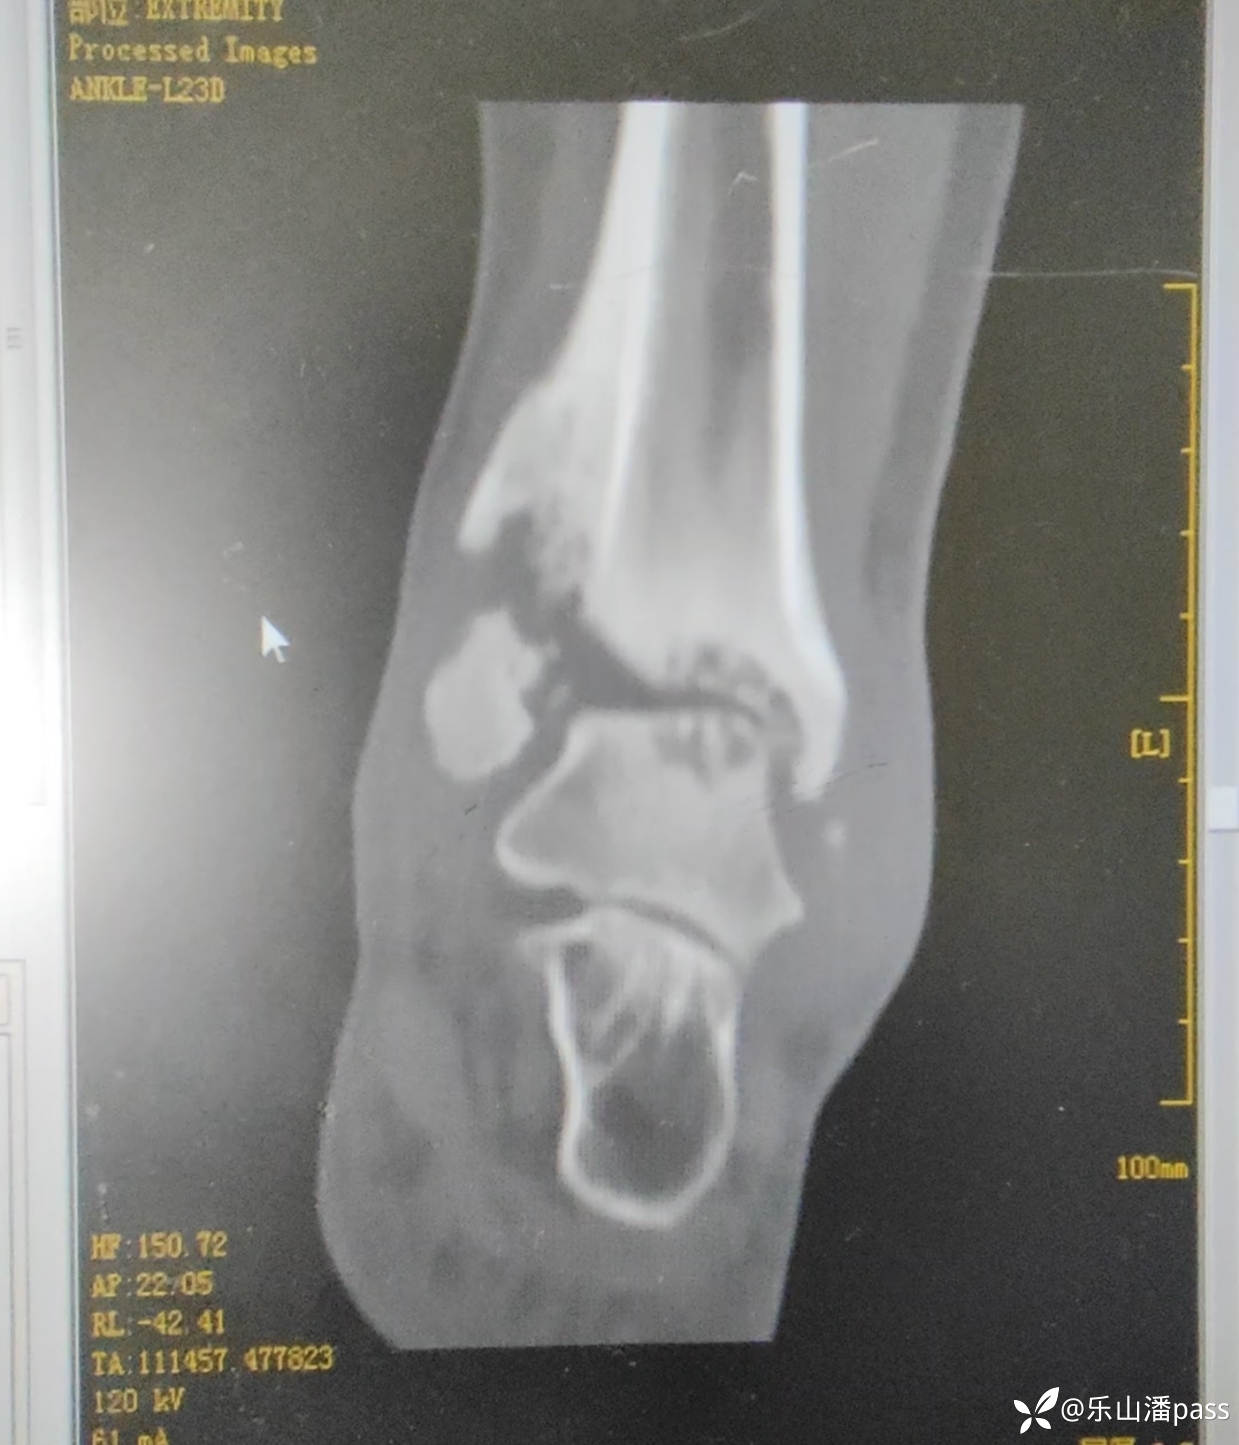

完善检查,排除感染等情况

img

拟手术治疗,方案?